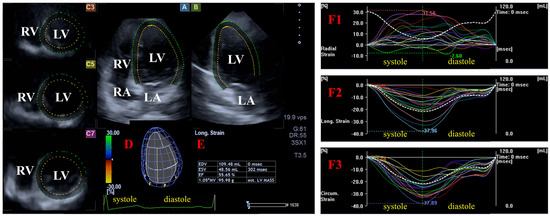

Three-dimensional speckle-tracking echocardiography. The same echocardiographic tool was used for 3DSTE after changing the transducer to a PST-25SX matrix phased-array transducer [9,10,11,12]. Then, 3D echocardiographic datasets were acquired from the apical window. To reach optimal image quality, 6 subvolumes within 6 cardiac cycles during a breathhold were acquired. Version 2.7 of 3D Wall Motion Tracking software (Ultra Extend, Toshiba Medical Systems, Tokyo, Japan) was used for the analysis of the auto-created merged 3D full-volume dataset. Apical four-chamber (AP4CH) and two-chamber (AP2CH) long-axis views and 3 cross-sectional views were automatically created, and then septal and lateral edges of the LV-MA and the endocardial surface of the LV apex were determined by the observer. Following automatic contour detection and sequential analysis, a virtual 3D model of the LV was created, and the following global and basal, midventricular, and apical regional unidirectional/unidimensional LV strains were calculated as a mean of segmental ones (Figure 2) [1,2,8,9,10,11,12]:

Figure 2.

Assessment of the left ventricular (LV) strains by three-dimensional (3D) speckle-tracking echocardiography. Apical four-chamber (A) and two-chamber (B) long-axis views and short-axis views at the basal (C3), midventricular (C5), and apical levels (C7) of the LV are presented together with a 3D cast of the LV (D) and the LV volumetric data calculated (E). Curves of time—global and segmental radial (F1), longitudinal (F2), and circumferential (F3) LV strains (white and colored lines) and time—change in the LV volume (dashed white line) during the cardiac cycle are shown together. Abbreviations: LA = left atrium; LV = left ventricle; RA = right atrium; RV = right ventricle; EDV = end-diastolic volume; ESV = end-systolic volume; EF = ejection fraction.